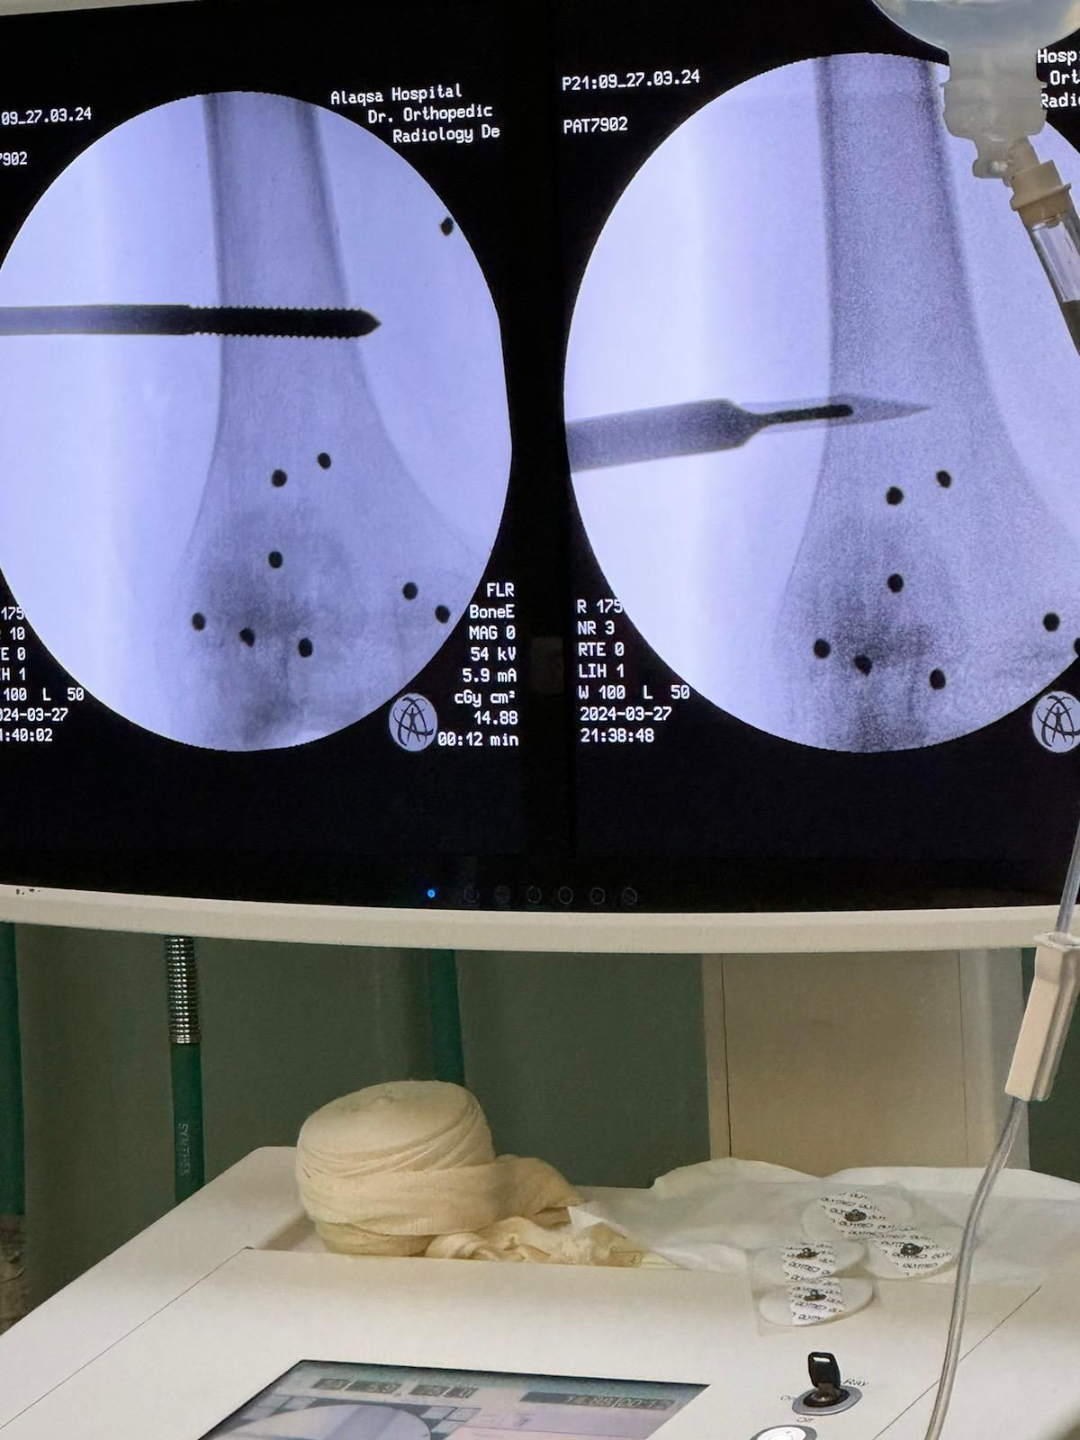

Every makeshift bed in makeshift tents in the hospital courtyard is filled to capacity with dismembered young men and young children. They target the legs of the young civilian men, horrific cruelty, subhanAllah.

The little bullets sprayed by drones on the little kids’ legs. If this cruelty isn’t a sign of genocide then I don’t know what is.